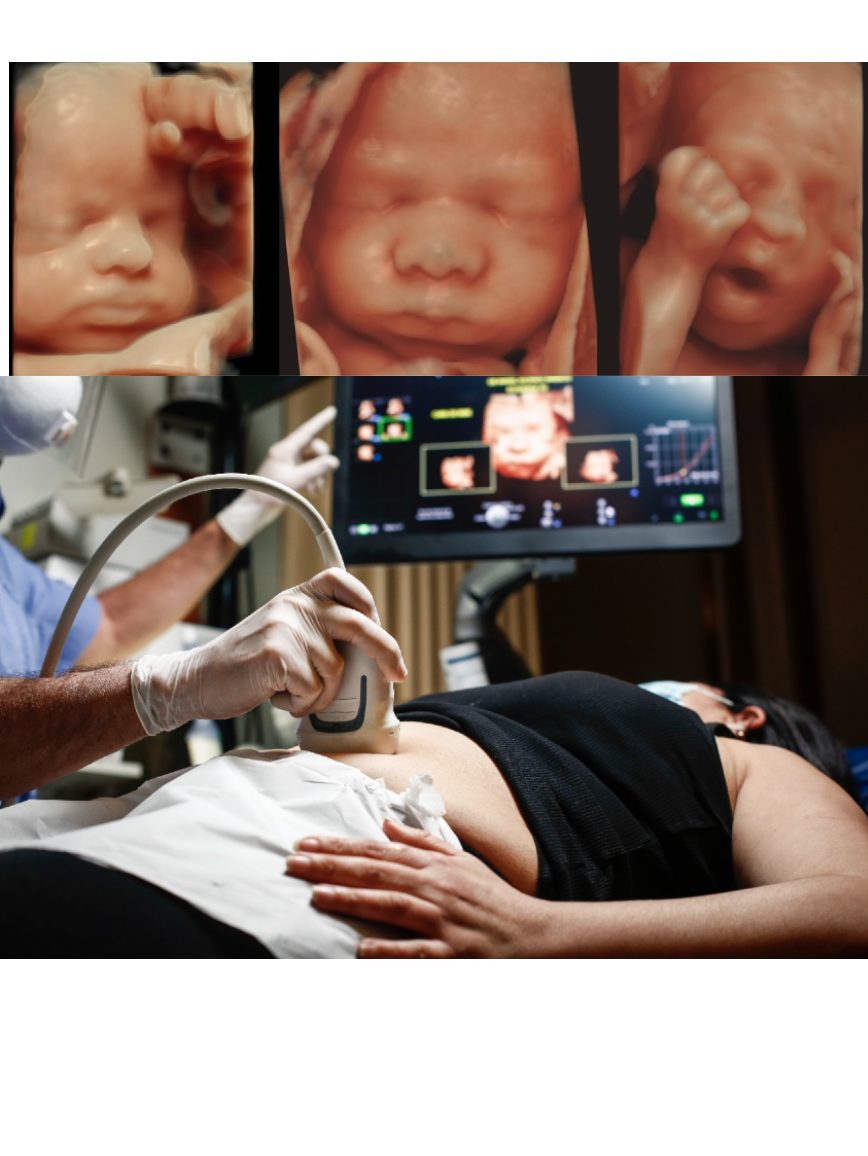

De una célula a un bebé. El desarrollo de un ser humano dentro del vientre materno es un proceso fascinante que hasta hace pocos años era imposible de monitorear con la escasa tecnología que había. Esto ha cambiado gracias a los nuevos ecógrafos que parecen sacados de la ciencia ficción. Hoy, ya podemos ver las estructuras internas de un feto de apenas 4 centímetros, así como su superficie corporal externa al detalle. Y todo en Full HD y en tiempo real.

Cada transductor está formado por hileras de cristales, que emiten vibraciones u ondas sonoras, los cuales viajan por los tejidos del bebe y permiten producir las imágenes que vemos en pantalla. A más cantidad de cristales, el detalle de la imagen es superior. Por ello, la Ecografía 7D es considerada la más moderna y precisa del mundo. Es 16 veces más rápida que un ecógrafo 4D (cuyo transductor tiene solo 980 cristales) y es capaz de capturar más de mil imágenes por segundo, dando una nitidez asombrosa. Por ello, el 7D más que una dimensión, es la evolución en la Definición.

Con la Ecografía 7D, este primer encuentro de la madre con su futuro bebé es mucho más especial pues los nuevos equipos capturan imágenes a velocidad real y en alta resolución, como si se pusiera una cámara dentro del útero materno. Ahora no solo se puede estudiar a detalle todas las estructuras y órganos del feto, sino también podemos captar muchos de sus gestos y movimientos, desde una sonrisa o hasta cuando sacan la lengua, algo que no se podía hacer con los antiguos ecógrafos.

“Con la ecografía a color 7D se puede observar la actividad y el buen desarrollo del bebe. La captura de la imagen es mucho más rápida, sobre todo en órganos como el corazón y el cerebro. Incluso, ya podemos ver a detalles los vasos sanguíneos, por más pequeñitos que sean. Sin duda, es el mejor método de diagnóstico para ver el bienestar fetal y al mismo tiempo lograr un encuentro anticipado entre los padres y su bebe”, explica el Dr. Rafael Ascenzo Aparicio, experto en ecografía fetal de la Clínica Miraflores.